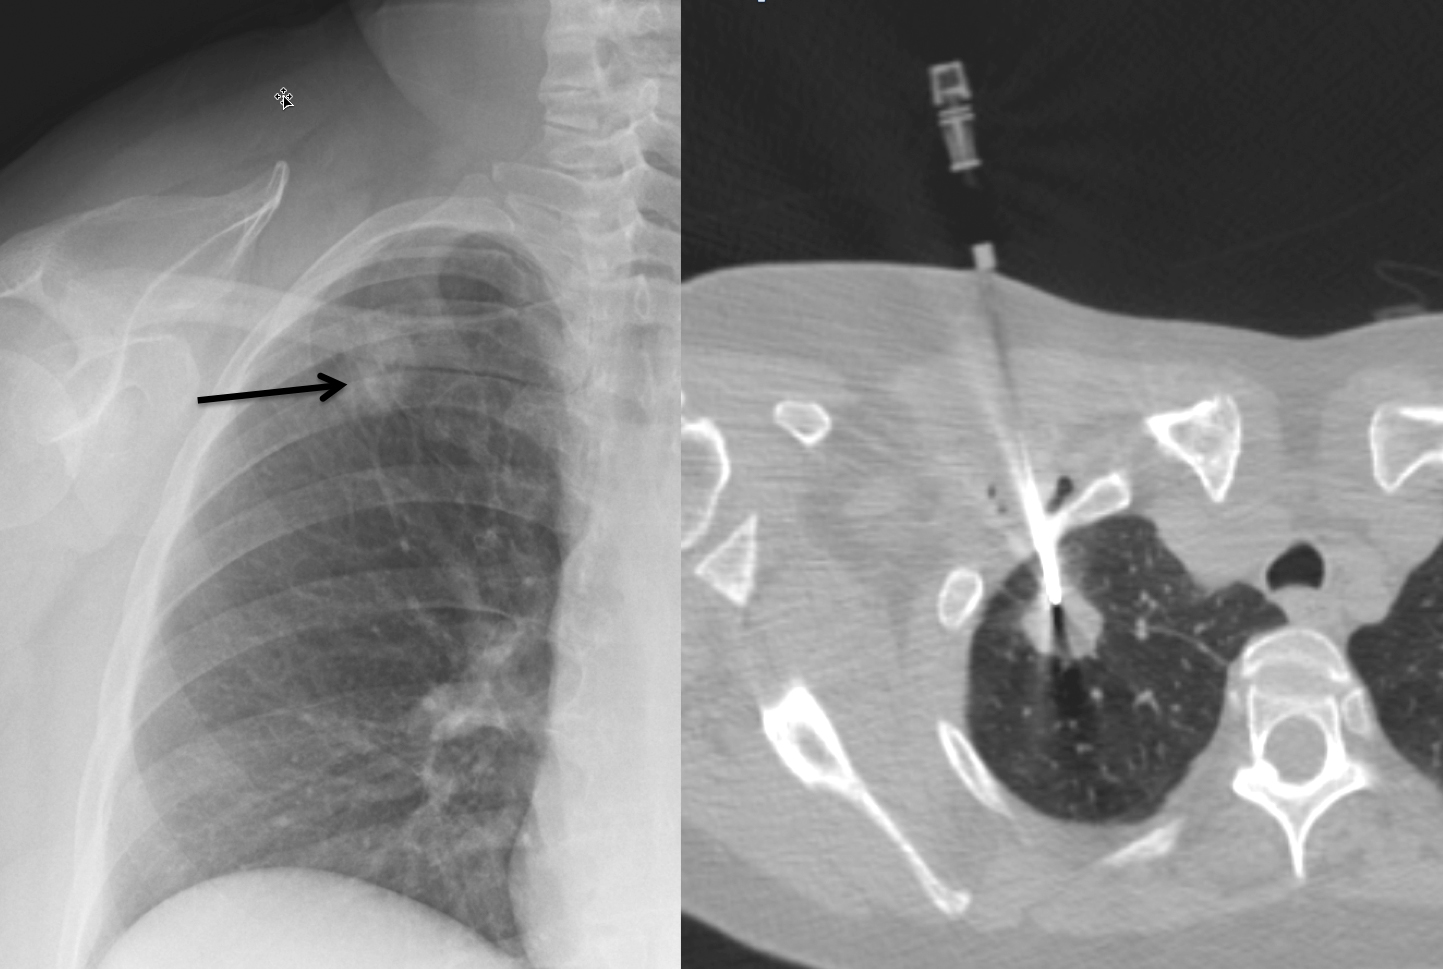

CT guidsed biopsy

CT guided biopsy